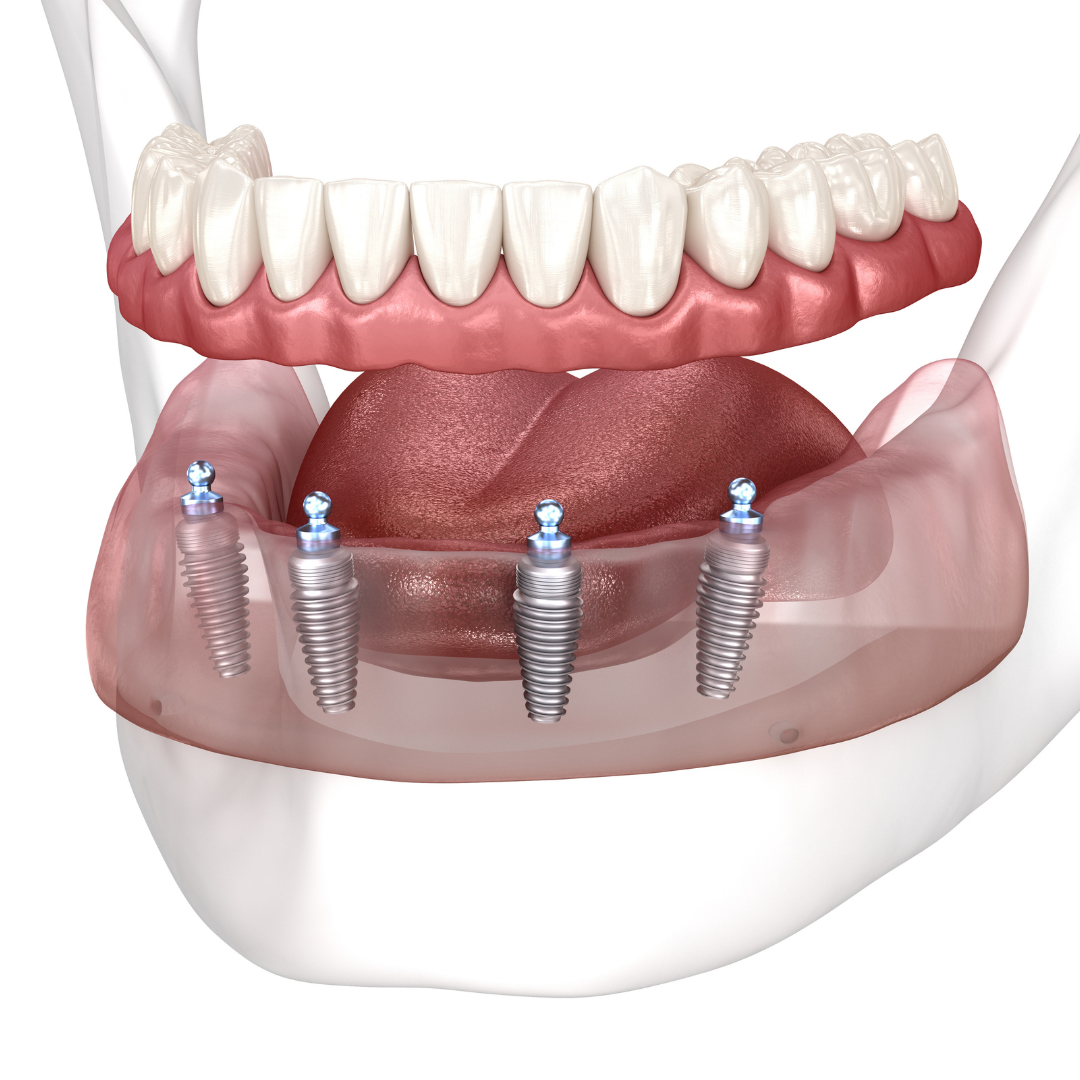

So, how do they work?

Every single dental implant consists of three parts - the implant, the abutment, & the crown. The implant is made of medical grade titanium. This part is surgically placed into the patient’s jaw bone and left to heal for 3-6 months afterwards.

This implant piece acts as the foundation for the rest of the tooth. Once the bone around the site has healed, the abutment and crown are placed on top of the implant. The end result is a beautiful, natural-looking new tooth!

Few people will ever be able to tell the difference between your implants and your real teeth.